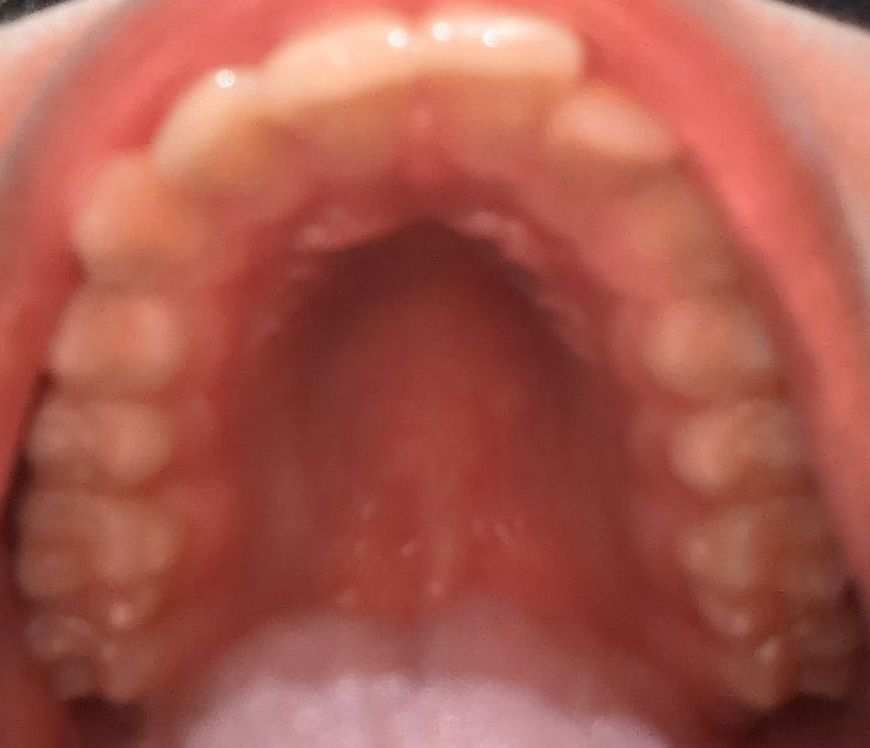

I do have breathing problems, however I have DNS asw so I'm not sure if that's the main cause or a narrow pallete

If I do get pallete expansion, should I expect any changes in my face? I'm almost 17.